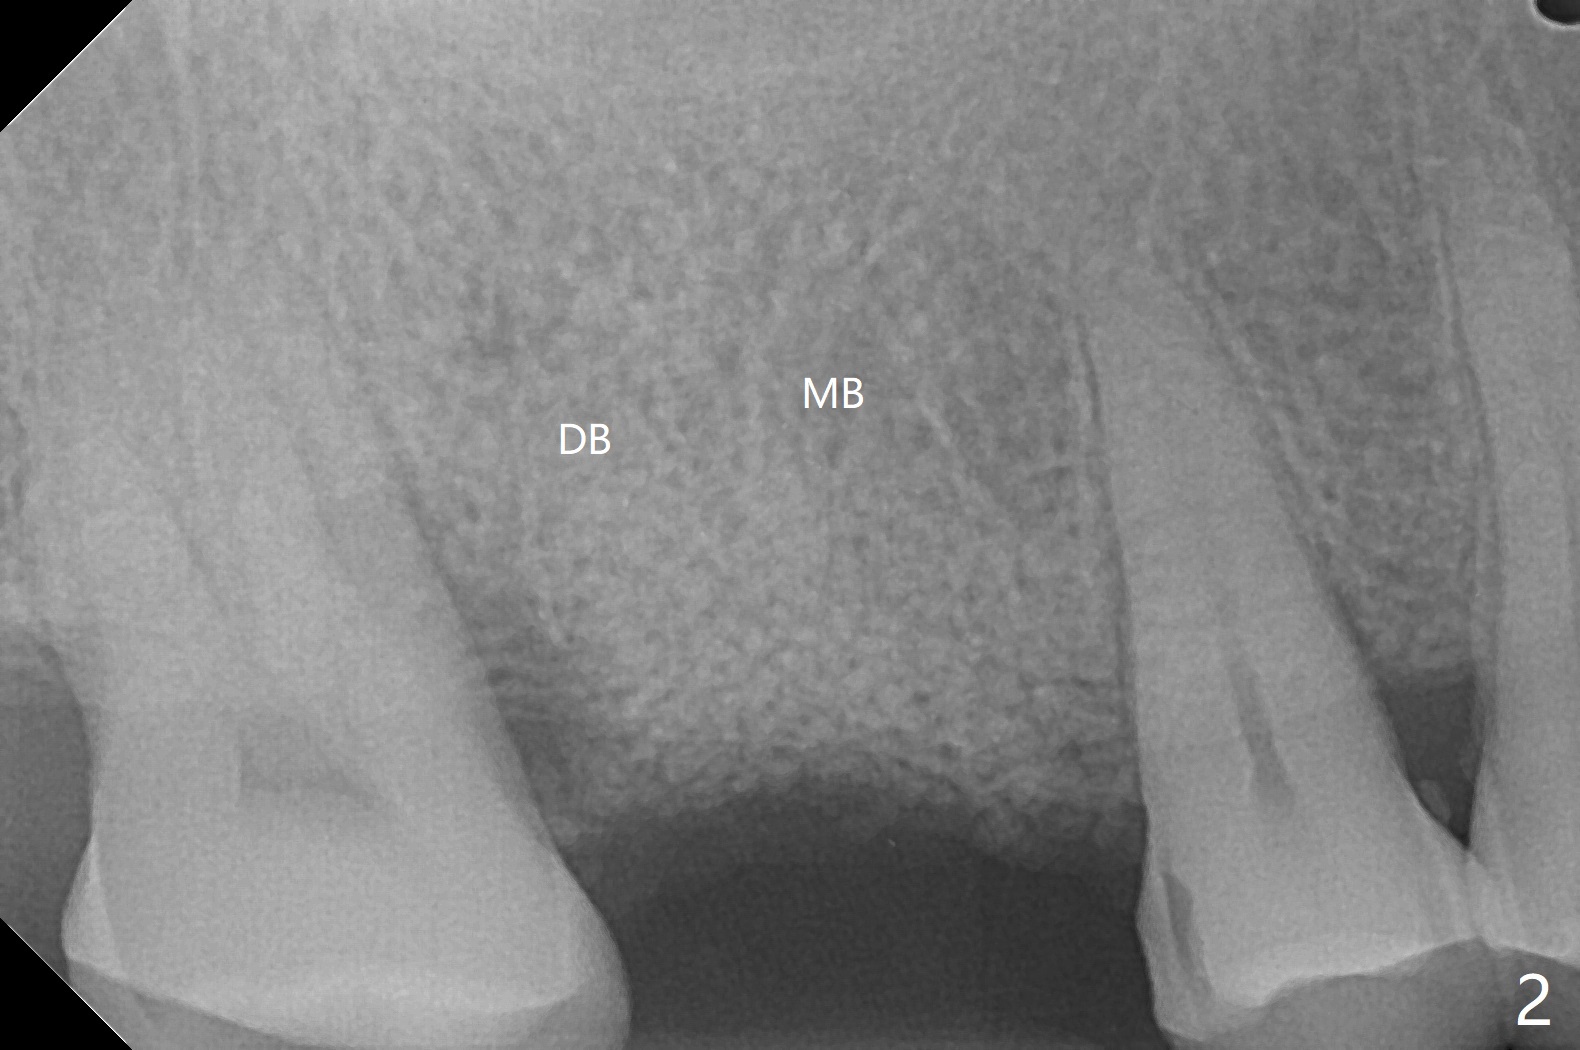

57岁女爱咬硬的东西,多个牙尖断裂(图一:*),由于左下6近中龋齿,远中根尖周炎(<),最近在右边咀嚼多,突然右上6出现严重疼痛,检查发现近中腭侧牙尖折裂,病人要求拔除,可能出血多,没有骨质吸收,骨粉好像没有填入腭侧窝,而近中颊侧,远中颊侧窝(图二:MB, DB)根尖部分充填少。今后拔牙清创采血后,每个牙槽窝里塞入含1:50,000肾上腺素小纱布,压迫止血,开始输入少量骨粉,用细的器械压入牙槽窝深部。术后一周牙周敷料脱落,伤口正常愈合(图三,四)。